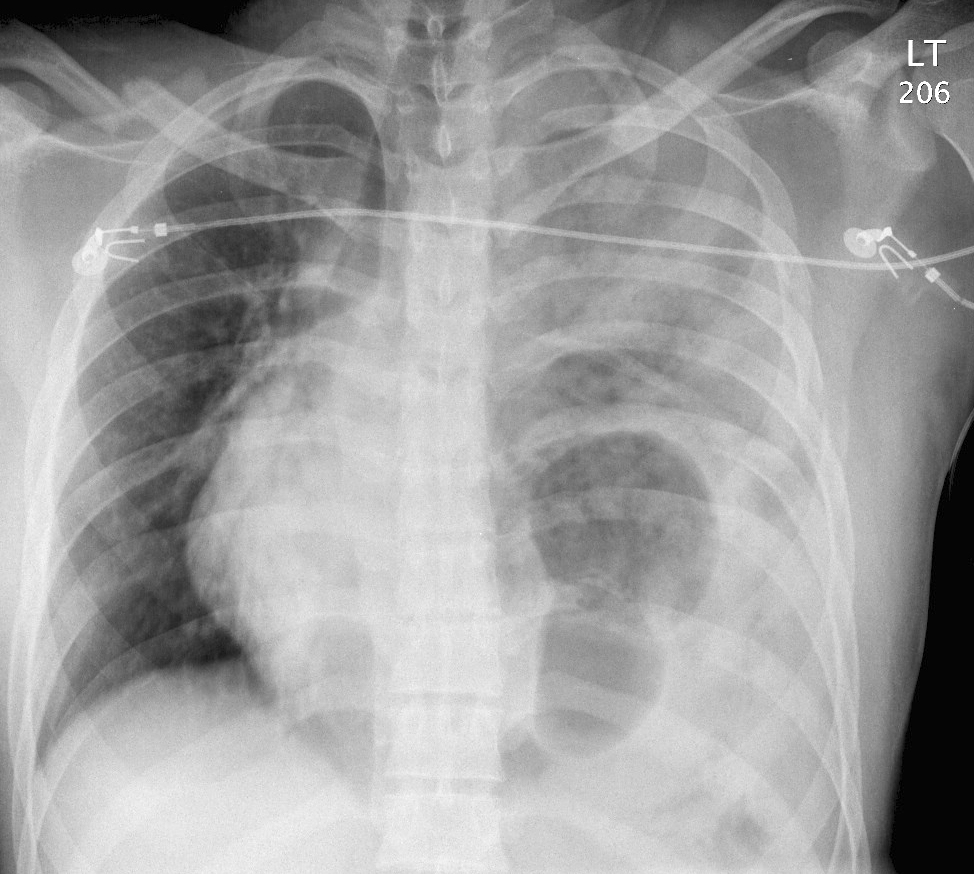

Gallery Blunt Chest Trauma Rupt HD Case 9a

Case 9a